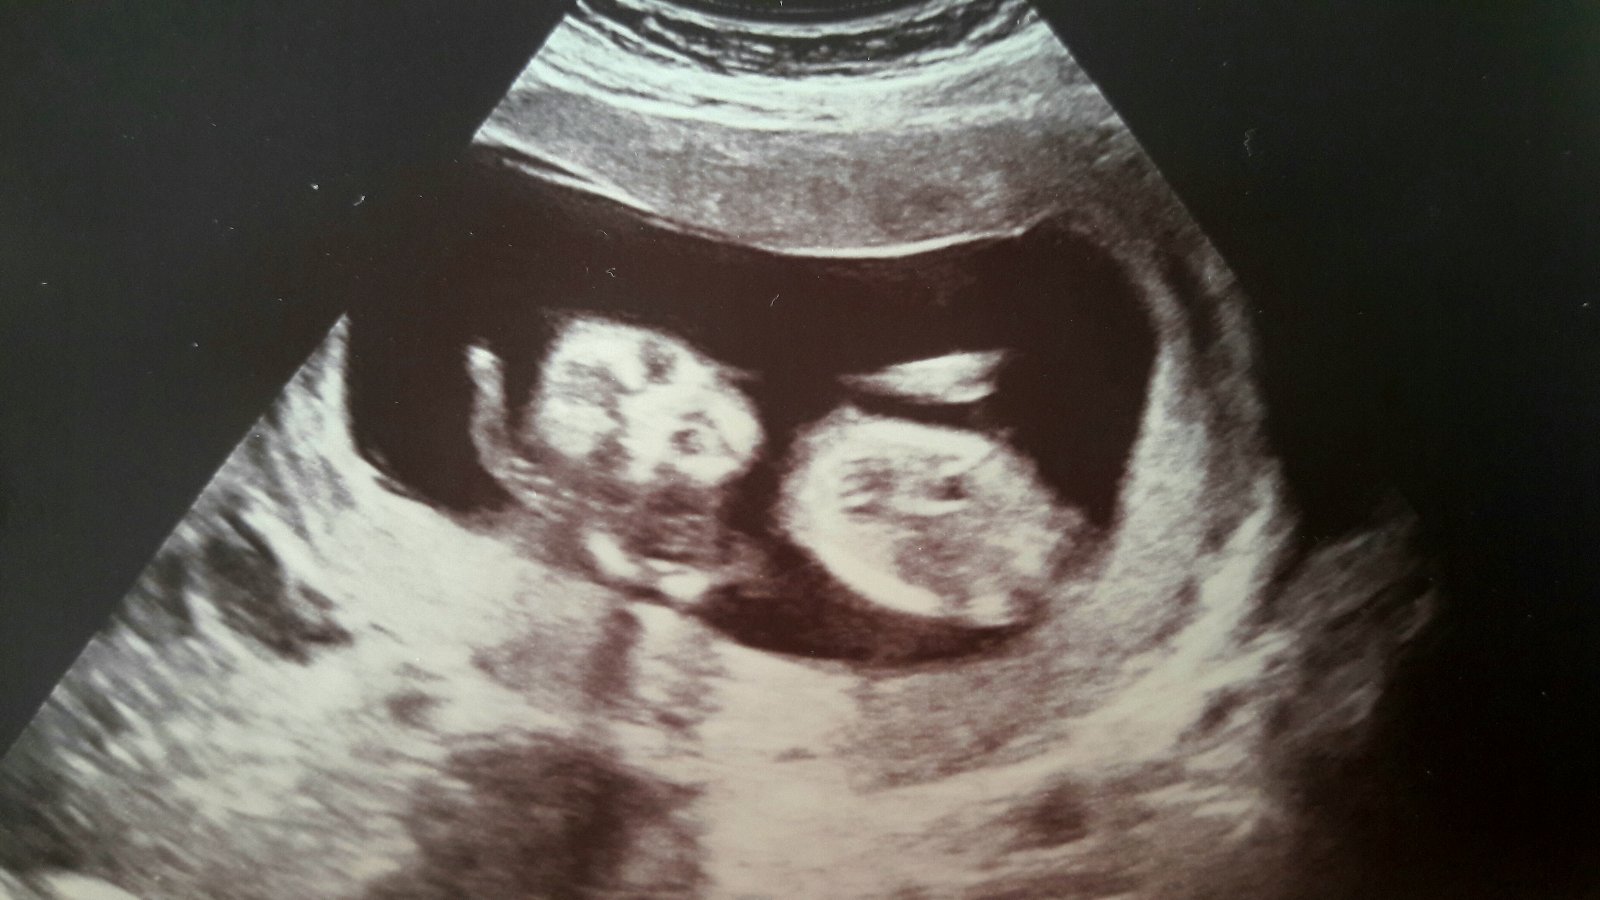

@juliia super!! Na tyhle fotky by člověk mohl koukat pořád, že 😊. Přeju samé zdravíčko, ať koblížek krásné roste a tobě je jen usměvavo 😊.